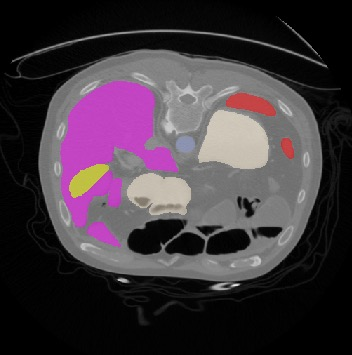

Transformers, the default model of choices in natural language processing, have drawn scant attention from the medical imaging community. Given the ability to exploit long-term dependencies, transformers are promising to help atypical convolutional neural networks (convnets) to overcome its inherent shortcomings of spatial inductive bias. However, most of recently proposed transformer-based segmentation approaches simply treated transformers as assisted modules to help encode global context into convolutional representations without investigating how to optimally combine self-attention (i.e., the core of transformers) with convolution. To address this issue, in this paper, we introduce nnFormer (i.e., Not-aNother transFormer), a powerful segmentation model with an interleaved architecture based on empirical combination of self-attention and convolution. In practice, nnFormer learns volumetric representations from 3D local volumes. Compared to the naive voxel-level self-attention implementation, such volume-based operations help to reduce the computational complexity by approximate 98% and 99.5% on Synapse and ACDC datasets, respectively. In comparison to prior-art network configurations, nnFormer achieves tremendous improvements over previous transformer-based methods on two commonly used datasets Synapse and ACDC. For instance, nnFormer outperforms Swin-UNet by over 7 percents on Synapse. Even when compared to nnUNet, currently the best performing fully-convolutional medical segmentation network, nnFormer still provides slightly better performance on Synapse and ACDC.